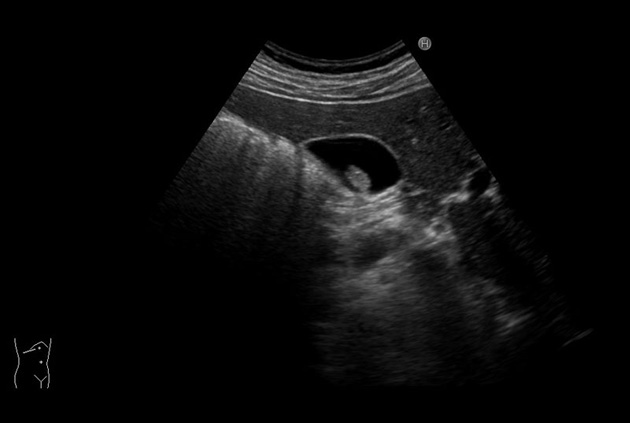

The Arietta 70 has many advanced and unique probes that fully cover the expanding range of procedures that benefit from ultrasound guidance.

Arietta 70’s ergonomics address every point of interaction between the ultrasound system and surgeon. In addition to its moveable control panel, adjustable monitor, and portable frame, the Arietta supports a set of lightweight, ergonomically-contoured and specifically designed surgical probes.